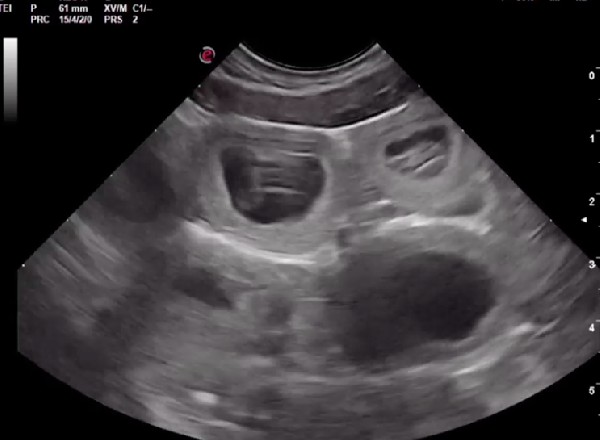

En plus de confirmer la gestation, elle permet de contrôler l’aspect des ampoules, des placentas, des ovaires et de l’utérus. Elle permet aussi d’estimer avec une bonne précision le nombre de chiots si elle est faite au moment optimal (autour de J25 post-ovulation). Si la date d’ovulation n’est pas connue, l’échographie peut permettre de dater la gestation grâce à différentes mesures anatomiques et à l’évolution des structures anatomiques visibles à l’échographie. Elle permet également de mettre en évidence et de suivre d’éventuelles résorptions embryonnaires et nous amène alors à réaliser d’autres examens.